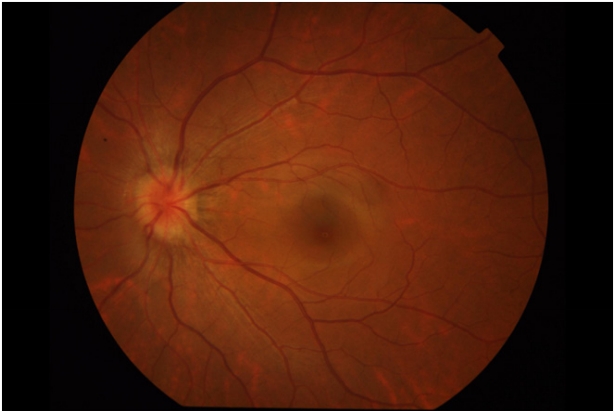

图 1 典型TDS患者眼底照片

Figure 1 Fundus photos of typical TDS patients

The optic disc is tilted downward, accompanied by a conus on the lower side of the optic disc, and the fundus below is atrophic.